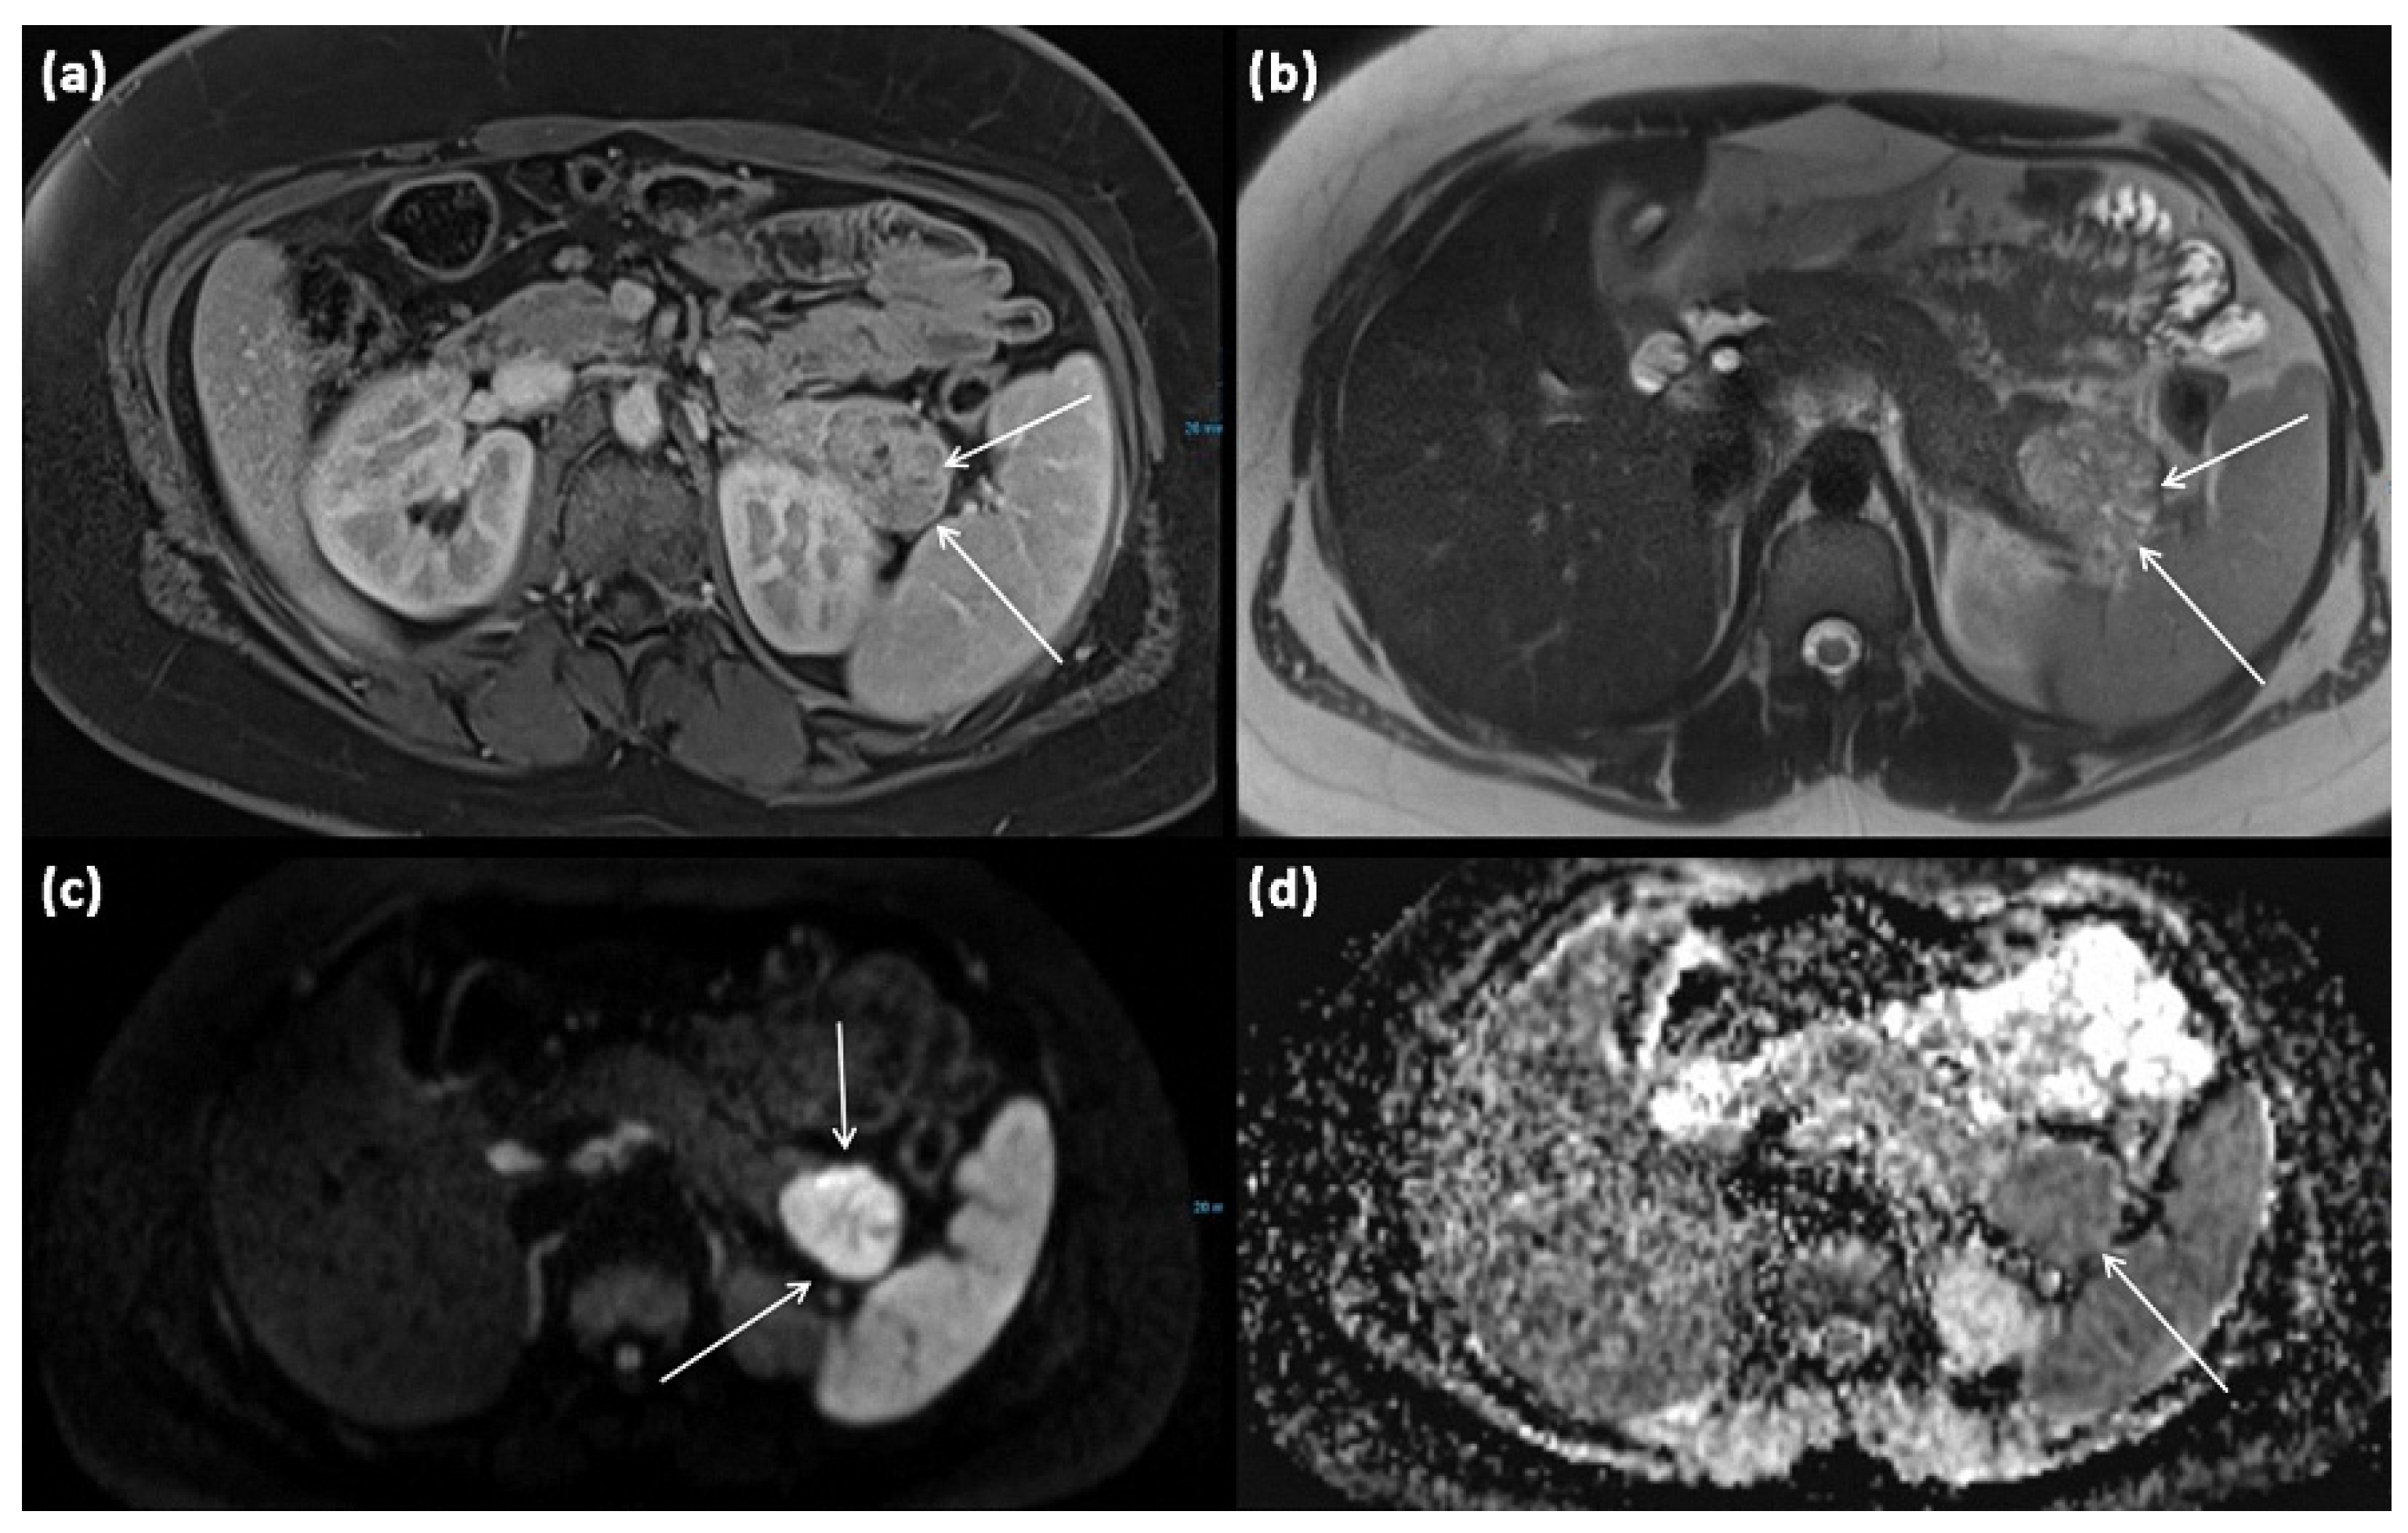

3.4. Cystic Tumors with Solid Portions: Solid Pseudopapillary Neoplasms (SPN)